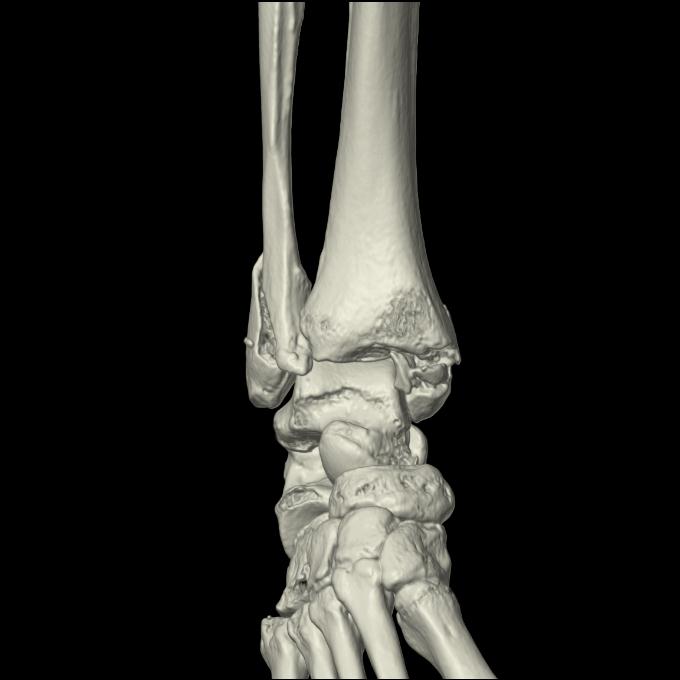

102755 1/4 2R 1/15 2R 右足関節 68歳女性 右三果脱臼骨折